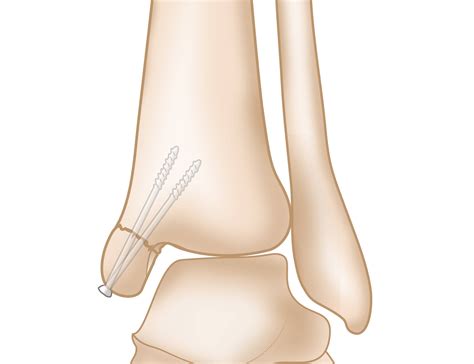

• Surgery: In cases of severe fractures, surgery may be required to realign the bones and stabilize the joint.

Ankle Fracture